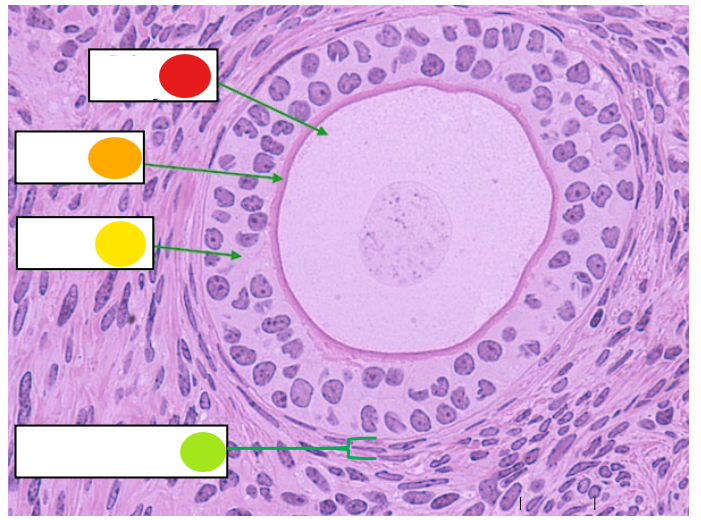

red

granulosa cells

orange

primary oocyte

what is this

primary follicle

red

granulosa cells

orange

thecal cells

yellow

zona pellucida

What is this

secondary follicle